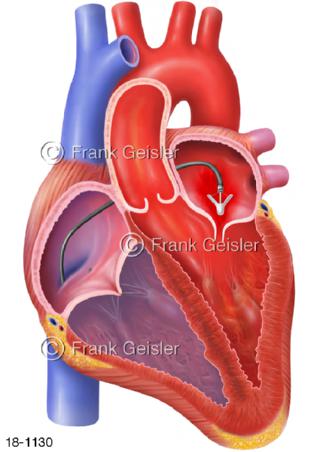

18-1130 Herz Mitralklappe Mitraklappeninsuffizienz